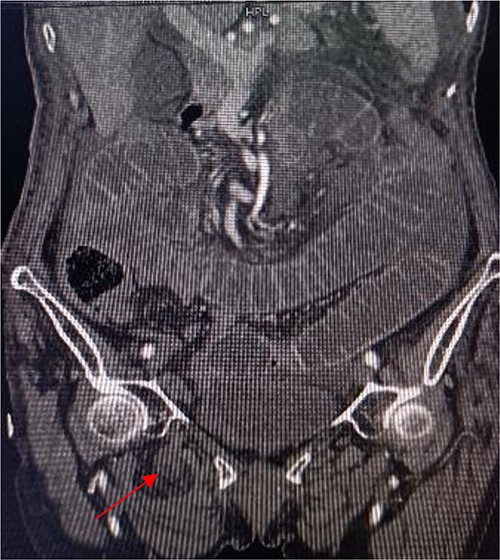

Tumor (indicated by black arrow) on the ascending colon observed during operation.

Laparoscopic exploratory laparotomy and obturator hernia repair were performed. A 4 × 4 cm thick hard tumor was observed in the ascending colon near the liver curve, involving serosa, and the ascending colon was partially blocked. A total of 80 cm away from ileocecum, the intestine entered from the right obturator hernia, causing obstruction and expansion of the proximal intestinal canal, congestion, and edema of the intestinal wall. We aspirated the ascites, loosened the adhesion around the obturator hernia ring, and returned the small intestine back into the abdominal cavity. It was observed that the intestinal wall of the hernia section was ~4 cm, necrotic, and broken, and the intestinal contents were flowing out, the intestinal defect was immediately closed, the abdominal cavity was flushed with normal saline, and the peritoneum at the obturator was intermittently sutured and repaired. A median abdominal incision of ~12 cm was used to cut each layer of the abdominal wall, enter the abdomen, protect the incision, lift out the intestine at the breach, place the aspirator in the intestinal lumen, aspirate large amount of intestinal contents, and temporarily close the breach. The abdominal and pelvic cavities were rinsed again with plenty of normal saline. With the consent of the patient’s family, a double-cavity ileostomy was successfully performed.